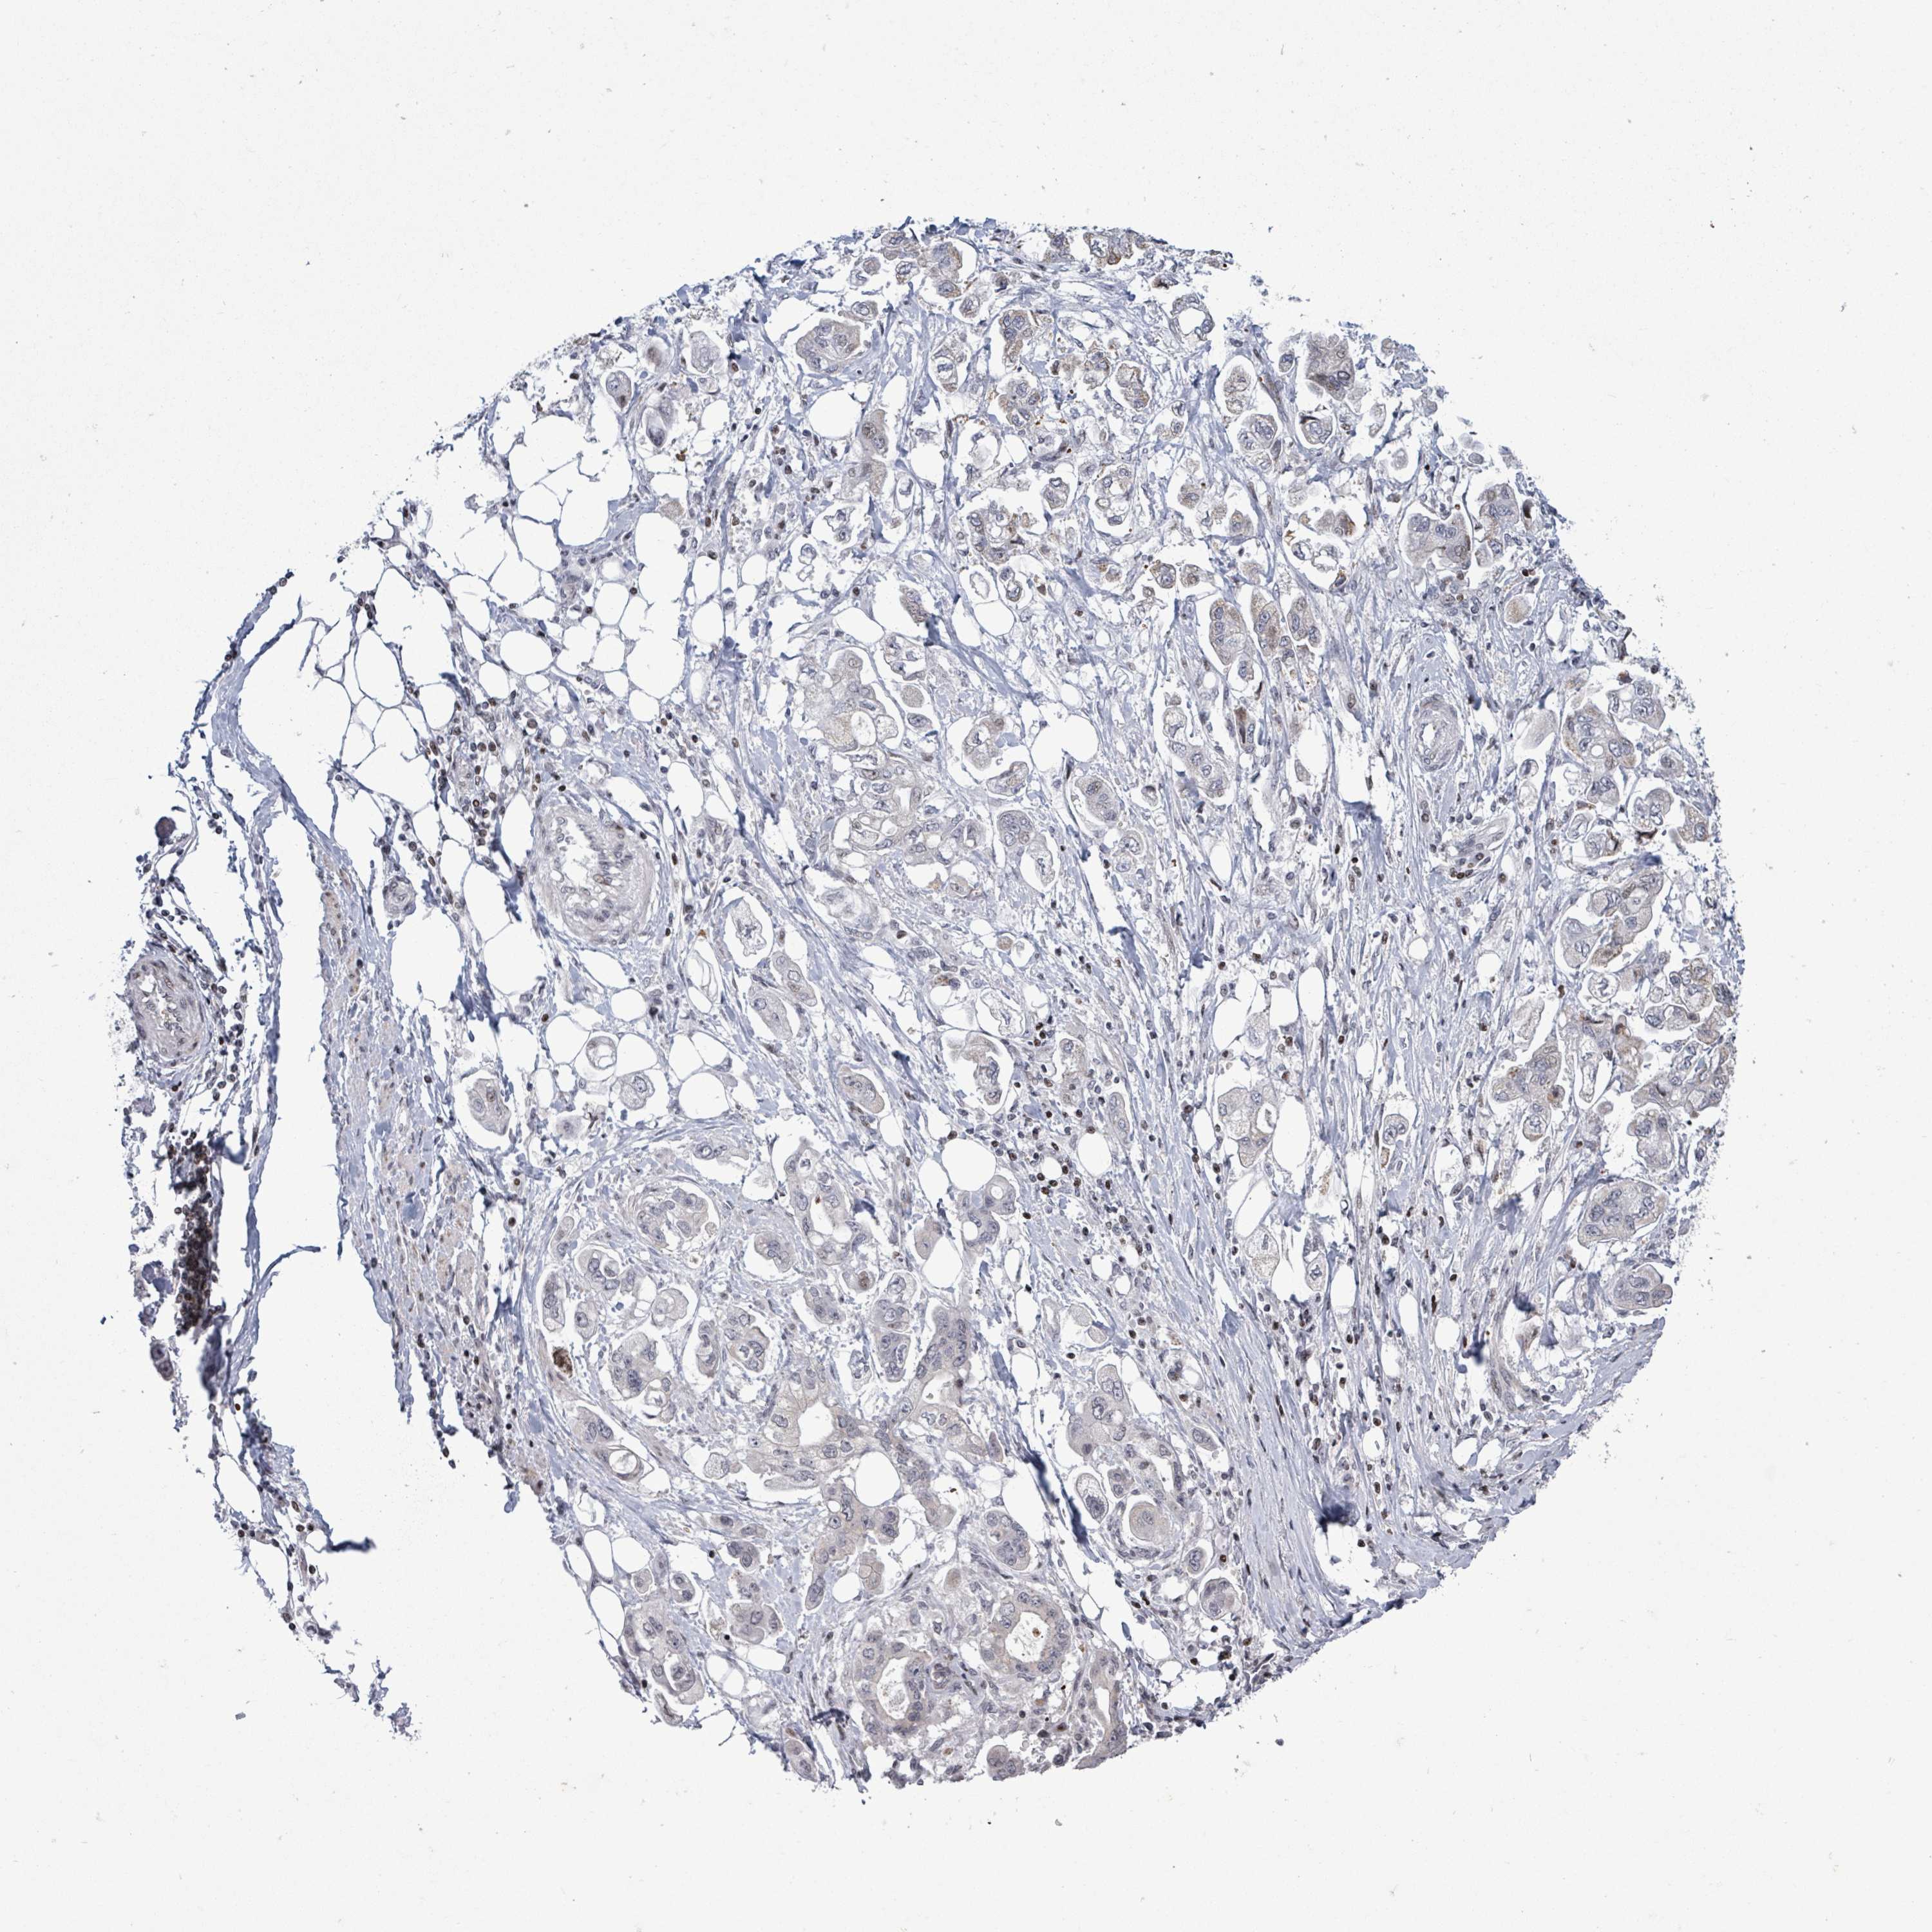

STOMACH CANCER - Protein expressioni

A mouse-over function shows sample information and annotation data. Click on an image to view it in a full screen mode. Samples can be filtered based on level of antibody staining by selecting one or several of the following categories: high, medium, low and not detected. The assay and annotation is described here.

Note that samples used for immunohistochemistry by the Human Protein Atlas do not correspond to samples in the TCGA dataset.

Antibody stainingi

Antibody staining in the annotated cell types in the current human tissue is reported as not detected, low, medium, or high, based on conventional immunohistochemistry profiling in selected tissues. This score is based on the combination of the staining intensity and fraction of stained cells.

Each image is clickable and will lead to virtual microscopy that enables deeper exploration of all samples and also displays staining intensity scores, fraction scores and subcellular localization as well as patient and tissue information for each sample.

Antibody HPA051804

Antibody HPA063581

Staining

High

Medium

Low

Not detected

Adenocarcinoma, NOS